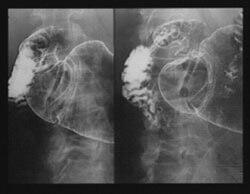

Dans un essai clinique en double aveugle portant sur 38 patients, des chercheurs ont constaté qu'une dose orale de 1 g de mastic par jour pendant une période de deux semaines entraînait un soulagement des symptômes dans 80 % des cas chez des patients avec un ulcère duodénal traité avec le mastic contre 50 % dans le groupe témoin. L'étude a également apporté des preuves endoscopiques que le mastic favorisait la guérison des tissus de la muqueuse gastrique. Les ulcères ont été complètement remplacés par des cellules épithéliales saines12. La guérison de l'ulcère a été complète chez 70 % des patients prenant le mastic contre 22 % dans le groupe placebo.

Des études animales ont également montré que le mastic possède des propriétés cytoprotectrices (protectrices des cellules) et antisécrétrices et qu'il peut diminuer les lésions de la muqueuse gastrique provoquées par les médicaments contre l'ulcère et l'aspirine. Ainsi, chez des rats chez lesquels des ulcères gastriques ou duodénaux ont été induits de façon expérimentale une dose de 500 mg de mastic/kg (équivalent chez l'homme à 500 mg par jour) réduisait les sécrétions gastriques, protégeait les cellules et diminuait les lésions de la paroi de l'estomac induites par différents procédés expérimentaux.

Élimination d'H. pylori

Des chercheurs ont rapporté que le mastic était un agent antibactérien efficace dans le traitement de Helicobacter pylori. Dans leur rapport, ils ont noté que même de faibles doses de gomme de mastic - 1 g par jour pendant deux semaines - pouvaient traiter les ulcères peptiques très rapidement. Ils ont constaté que le mastic agissait contre Helicobacter pylori, ce qui pourrait expliquer ses effets thérapeutiques chez des patients atteints d'ulcères peptiques13.

Des chercheurs ont réalisé des tests in vitro qui ont révélé que le mastic tuait efficacement 99,9 % d'H. pylori lorsqu'il était testé contre différentes souches - NTCC 11637 (une souche de référence standard) et six isolats cliniques en incluant trois résistantes au métronidazole.

Il faut souligner que le mastic était également efficace contre les souches d'H. pylori résistantes au médicament, même à très faibles concentrations. Ces résultats suggèrent que le mastic a des activités antibactériennes très nettes contre H. pylori. Ces activités pourraient au moins en partie expliquer les propriétés anti-ulcéreuses du mastic.